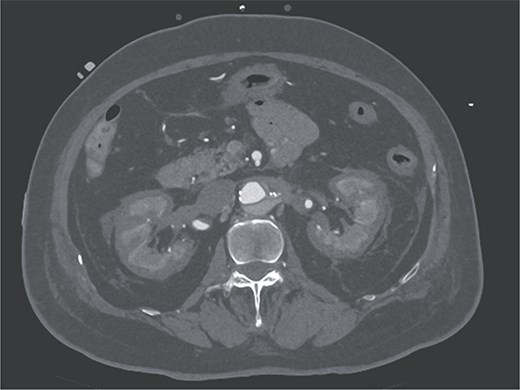

Contrast-enhanced CT image acquired on postoperative Day 2, showing the reverse rim sign.

A 70-year-old woman presented to the emergency department with sudden-onset chest and back pain. Contrast-enhanced CT revealed an ATAAD extending from the ascending aorta to the bilateral common iliac arteries. The primary entry tear extended from the ascending aorta into the aortic arch, and the false lumen remained patent throughout its entire peripheral extent (Fig. 1). Both renal arteries originated from the true lumen, and there was no malperfusion. Vital signs were stable, and the patient was not in shock. The patient underwent emergency total arch replacement with FET implantation using a 27 × 90 mm FROZENIX four-branched graft (Japan Lifeline Co., Ltd, Tokyo, Japan). The procedure was completed in 7 h and 6 min without intraoperative complications. Postoperatively, urine output declined markedly. Serum creatinine increased from a baseline of 0.81 to 2.61 mg/dl on postoperative Day 1. Diuretics failed to improve urine output, and renal replacement therapy was initiated. Contrast-enhanced CT on postoperative Day 2 showed no signs of renal malperfusion. Although the renal medulla exhibited normal enhancement, a diffuse non-enhancing area throughout the renal cortex—referred to as the “reverse rim sign”—was observed, consistent with RCN (Fig. 2). Thrombosis of the false lumen in the descending thoracic and thoracoabdominal aorta had progressed (Fig. 3). The patient developed persistent coagulopathy, with sustained hypofibrinogenemia and thrombocytopenia. On postoperative Day 2, the platelet count was 4.1 × 104/μl, D-dimer 13.5 μg/ml, and PT-INR 1.54, yielding an International Society on Thrombosis and Hemostasis DIC score of 6, consistent with overt DIC. Anticoagulation therapy with heparin and warfarin was administered. Ultimately, by postoperative Day 50, a total of 36 units of fresh frozen plasma and 100 units of platelets had been transfused; however, coagulation parameters gradually normalized thereafter, and no further transfusions were required (Fig. 4). A follow-up CT on postoperative Day 21 demonstrated further remodeling of the thrombosed false lumen. Brain magnetic resonance imaging performed on postoperative Day 9 to investigate delayed emergence revealed multiple scattered small acute ischemic infarctions involving the cerebellum, brainstem, and cerebral cortex (Fig. 5). These were not attributed to large-vessel occlusion but rather to systemic microthrombotic emboli. Despite supportive care, renal function did not recover, and maintenance dialysis was initiated. The patient was transferred to another hospital on postoperative Day 182.

DIC is frequently associated with acute kidney injury. Among them, RCN represents the most severe form, frequently resulting in irreversible renal failure. RCN is characterized by widespread coagulative necrosis due to decreased cortical perfusion. The renal cortex is more vulnerable to ischemia than the medulla because of its limited collateral circulation [4]. The “reverse rim sign,” defined by preserved medullary enhancement with cortical non-enhancement on contrast-enhanced CT, is a hallmark and highly specific imaging finding for RCN [5]. In DIC-associated RCN, systemic microthrombosis and regional hypoperfusion often cause irreversible cortical necrosis, leading to the need for long-term dialysis or kidney transplantation. In this case, RCN developed despite the absence of prolonged hypotension or renal artery malperfusion, suggesting a strong association with DIC. Diffuse RCN, as seen in the present case, is associated with worse renal outcomes than patchy RCN [6]. The advantage of diagnosing RCN, as opposed to typical acute kidney injury, is the ability to predict poor renal prognosis early on, allowing for earlier preparation for maintenance dialysis.